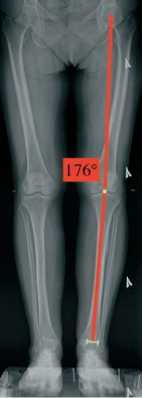

Пациенткам выполнена телерентгенография обеих нижних конечностей в положении стоя. На данных рентгенограммах определяли механическую ось нижней конечности и угол HKA (англ.: Hip-Knee-Ankle). Данный угол измеряется между двумя линиями которые проводятся от центра головки бедренной кости и центра блока таранной кости до центра коленного сустава. (рис. 2)

Рисунок 2 . Телерентгенограмма пациента Б. Методика измерения угла HKA

При анализе зависимости показателей KOOS после операции от угла НКА, были установлены статистически значимые различия (p=0,020) (используемый метод: Критерий Краскела – Уоллиса) (рис. 9).

Рисунок 9. Влияние угла HKA (в градусах) после операции на показатели KOOS

В то же время, в ряде случаев, после оперативного вмешательства сохраняются неоднозначные клинические результаты, несмотря на удовлетворительную МРТ-картину. Так в работе G. R. Jackson et al. [22] продемонстрировали, что общая частота осложнений при рефиксации корня медиального мениска составила 10,4 %, однако только 1.4 % потребовалась конверсия в тотальную артропластику сустава. В нашей работе (табл. 4) при оценке неудовлетворительных результатов отмечено, что среднее значение HKA у этих пациентов составило 174,50° (173,00° – 175,25°) и имела средний показатель KOOS 65,2±8,4 балла. Схожие результаты опубликованы в статье K.S. Chung et al. [23], которые при долгосрочном наблюдении отметили, что худший функциональный результат был получен у пациентов с варусной деформацией, составляющей (175,3±1,8)°. J.H. Ahn et al. [24] провели исследование и пришли к тем же выводам, при варусной деформации >5° (>175°), результаты лечения сопоставимы с консервативным лечением. Таким образом, пациенты с углом HKA <175° могут рассматриваться как «контрольная» подгруппа с неблагоприятными исходами, что подчеркивает необходимость предоперационной коррекции оси конечности.